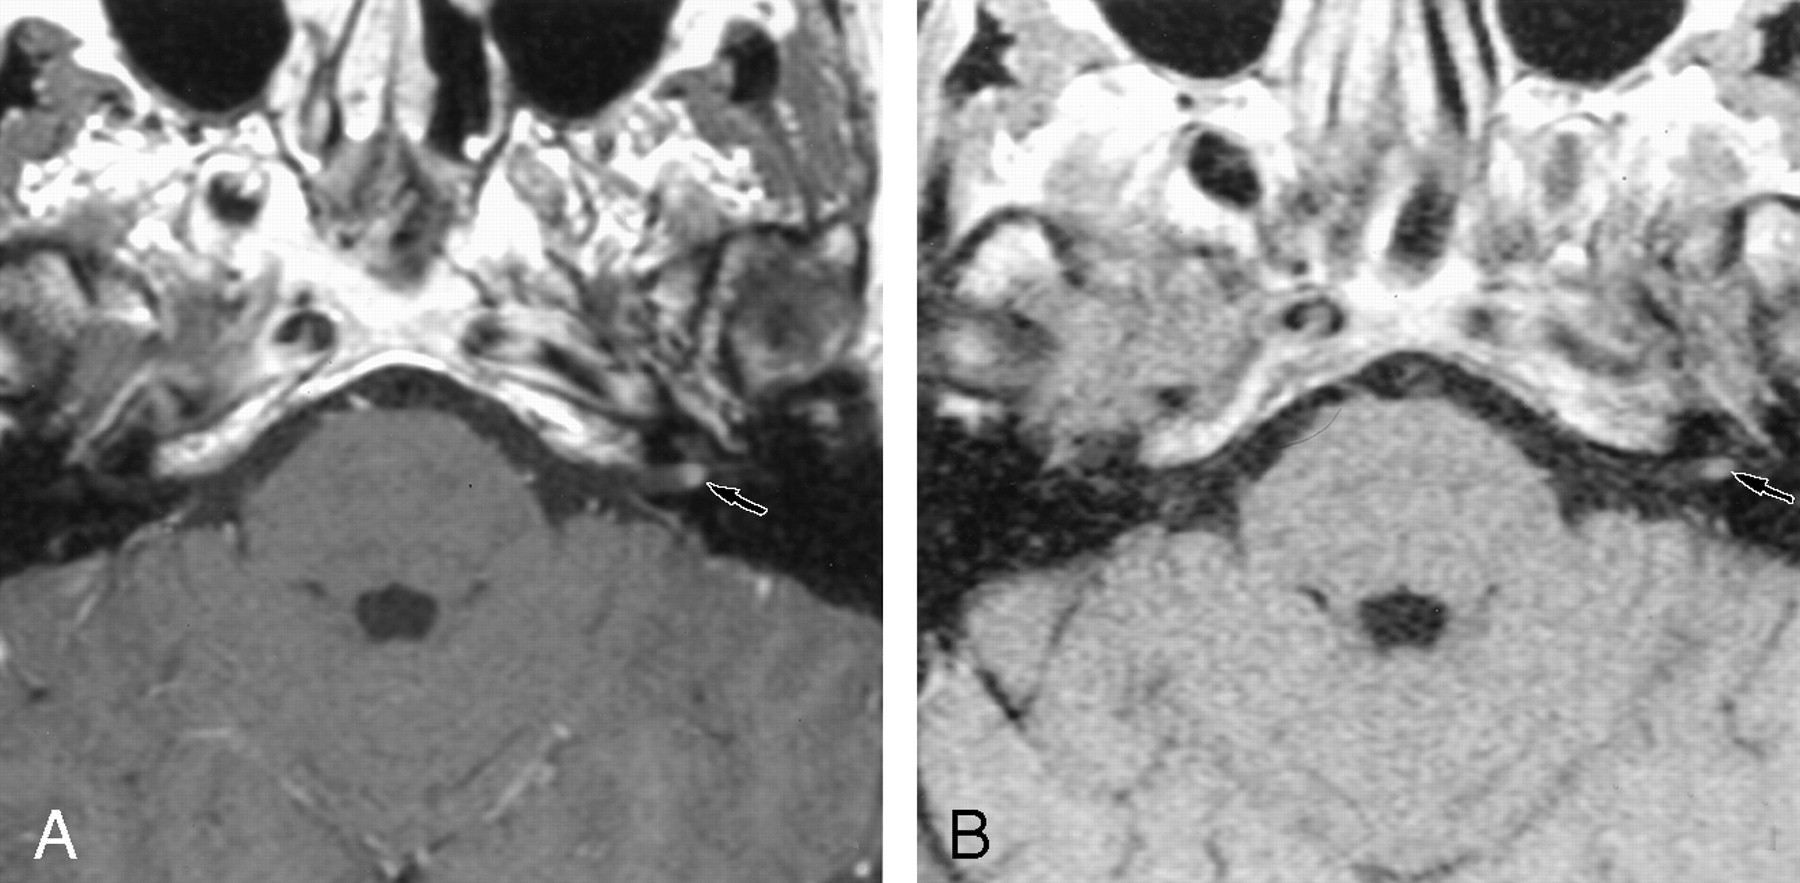

Retrocochlear tumors, whether vestibular schwannoma or other tumors of the CPA, were all detected on the 0.2-T images, even when they were very small (2 mm) (Fig 1). Two small intralabyrinthine schwannomas were seen on 0.2-T MR images (Fig 2). The five nontumoral undetected pathologic conditions were due to meningeal enhancement in the IAC (Fig 3), or facial nerve enhancement (Fig 4). The analysis of concordance between the 1.5- and 0.2-T yielded an excellent κ value that ranged from 0.93 to 0.95, depending on the observer.

A, The 1.5-T image (550/20/3) shows a posterior enhancement of the right labyrinth (arrow), which corresponds to a schwannoma in the vestibule.

B, The 0.2-T image (650/15/3) obtained at the same level depicts this intravestibular schwannoma (arrow).